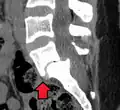

Anterolisthesis L5/S1